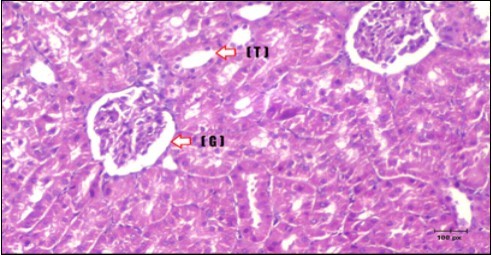

Kidney Histopathological Observations

Kidney sections of diabetic rats showed an increase in mesangial cell and matrix of glomeruli with increase in glycogen deposition and hyalinization of arterioles with thickened basement membranes of proximal and distal convoluted tubules. These changes will lead to progressive reduction in the filtration surface of the glomeruli 35. Histological examination of the kidney of the control rats showed normal structure of renal glomerular. The proximal and distal tubules were lined with normal epithelium (Figure 13). The diabetic rats showed tubular casts, inflammatory cellular infiltration and glomerular atrophy (Figure 14). Kidney of rats in groups (3 and 4) showed some glomeruli return to be normal (G). Focal tubules casts (T) in Fenugreek group and some normal tubules in the Glimepiride group with no inflammatory cellular infiltrate in both groups (Figure 15 and Figure 16). However, kidney of rats in group (5) showed normal glomerular (G), normal tubules (T) with no tubular casts (Figure 17).

Figure 16.Photomicrogragh of kidney section of treated rat with Glimepiride showing improvement of Bowman,s capsules and partial improvement of glomerulir (arrow) and completely return of distal tubules and proximal tubules to the normal shape with wide urinary space. (H&E) (40X).

Figure 17.Photomicrogragh of kidney section of treated rat with both Fenugreek and Glimepiride showing improved cortical tissue with most of both Bowman,s capsules (arrow) and proximal tubules (dash-arrow) with nearly normal structure .Note distal tubules still suffering (star). (H&E) (40X).